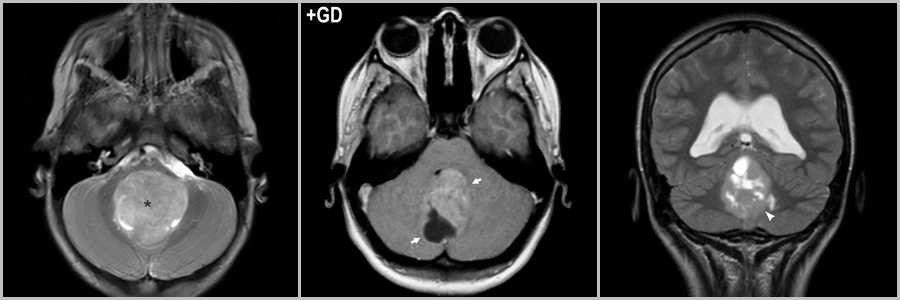

Гемангиобластома

Гемангиобластома — кистозная опухоль с мелким пристеночным узлом, располагается инфратенториально, может встречаться интрамедуллярно в спинном мозге, ассоциирована с болезнью фон Гиппеля-Линдау, при которой обнаруживается поражение других органов и систем, в частности почек (поликистоз) и надпочечников (феохромоцитома). При перфузионном исследовании отмечается выраженное превалирование показателей гемодинамики (rCBF и rCBV) у гемангиобластомы над пилоцитарной астроцитомой . Кроме того, астроцитома встречается чаще у детей и подростков, а гемангиобластома — у взрослых.

Рис.10 * Рис. 10 был заимствован из “Диагностическая нейрорадиология” 2009г. Корниенко В.Н., Пронин И.Н. 2009г. с целью наглядной демонстрации патологического процесса.

Мелкая гемангиобластома в области левой мозжечковой миндалины (стрелка на рис.10). После внутривенного контрастирования происходит интенсивное накопление контраста в пристеночном сосочке (стрелка на рис.10). Объёмный мозговой кровоток гемангиобластомы (стрелка на рис.10) существенно превышает те же показатели пилоцитарной астроцитомы (головка стрелки на рис.10).